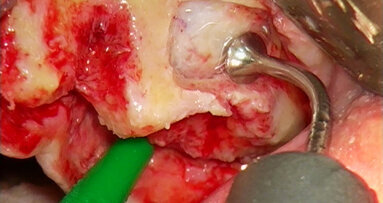

Při výkonech dentoalveolární chirurgie používáme koncovky osteoplastické, jejichž pomocí lze šetrně odpreparovat kostní tkáň nad retinovanými zuby ať v případě jejich následující extrakce nebo v případě následné fenestrace či tunelizace, kdy je možné jejich následné ortodontické zařazení do zubního oblouku.

Opatrnost doporučujeme při preparaci v blízkosti skloviny – pokud totiž dojde k přímému kontaktu piezochirurgické koncovky se sklovinou zubu, nelze vyloučit rozvoj mikrofraktur skloviny, která má odlišné mechanické vlastnosti než kost.

Osteotomické koncovky používáme pouze k separaci zubních tkání, které budeme závěrem extrahovat. S výhodou pro situace, kdy plánujeme okamžitou implantaci, je provedení extrakce pomocí piezochirurgie, ne však způsobem, který je často demonstrován na různých školeních a workshopech. Tam bývá stomatologům často doporučováno použití extrakční koncovky místo periotomu. To může vést k přehřátí okolní kosti a následným komplikacím ve smyslu alveolitis sicca. Extrakce v těchto situacích by měla být provedena jako postupná separace kořene a jeho odstranění po částech, přičemž okolní kostní tkáně se snažíme dotýkat minimálně, abychom nepoškodili kostní buňky zubního lůžka.